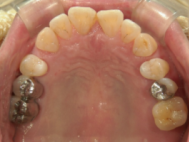

症例写真